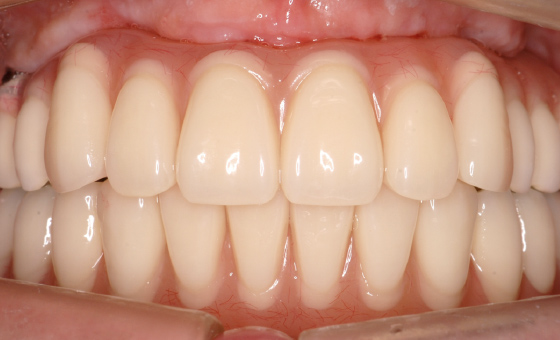

歯を失い、何か治療をしなければいけないけれど、費用面・手術のリスクが心配でインプラントではなく、入れ歯しか選択肢がないと思っていました。無料相談会に参加し、それぞれの治療のメリット・デメリットについて隠さず全て丁寧に説明してくださり、抱えていた不安が安心に変わりインプラント治療を受ける決断ができました。実際にインプラントにしてみて、歯を失う前のように食事をすることができ、仕上がりも自然で見た目が気になることもありません。吉岡先生にはこれからもメンテナンスでお世話になります。本当にありがとうございます。

インプラントは、歯を失った顎の骨に人工の歯根を埋めることで、セラミックなどの被せ物をする治療です。

歯を失った場合に行われるブリッジや入れ歯などの他の治療と比較し、インプラントの快適さ、天然歯に近い仕上がりといった良さが知られるにつれ、インプラント治療を選択する患者様が年々増えてきています。歯が元々骨に埋まっていたように、人工歯根を骨に埋めるため、ご自分の歯が蘇ったような感覚、見た目が再現できるのが特徴です。

歯を1本失ったケースから全て失ったケースまで、あらゆる状態に対応することが可能です。